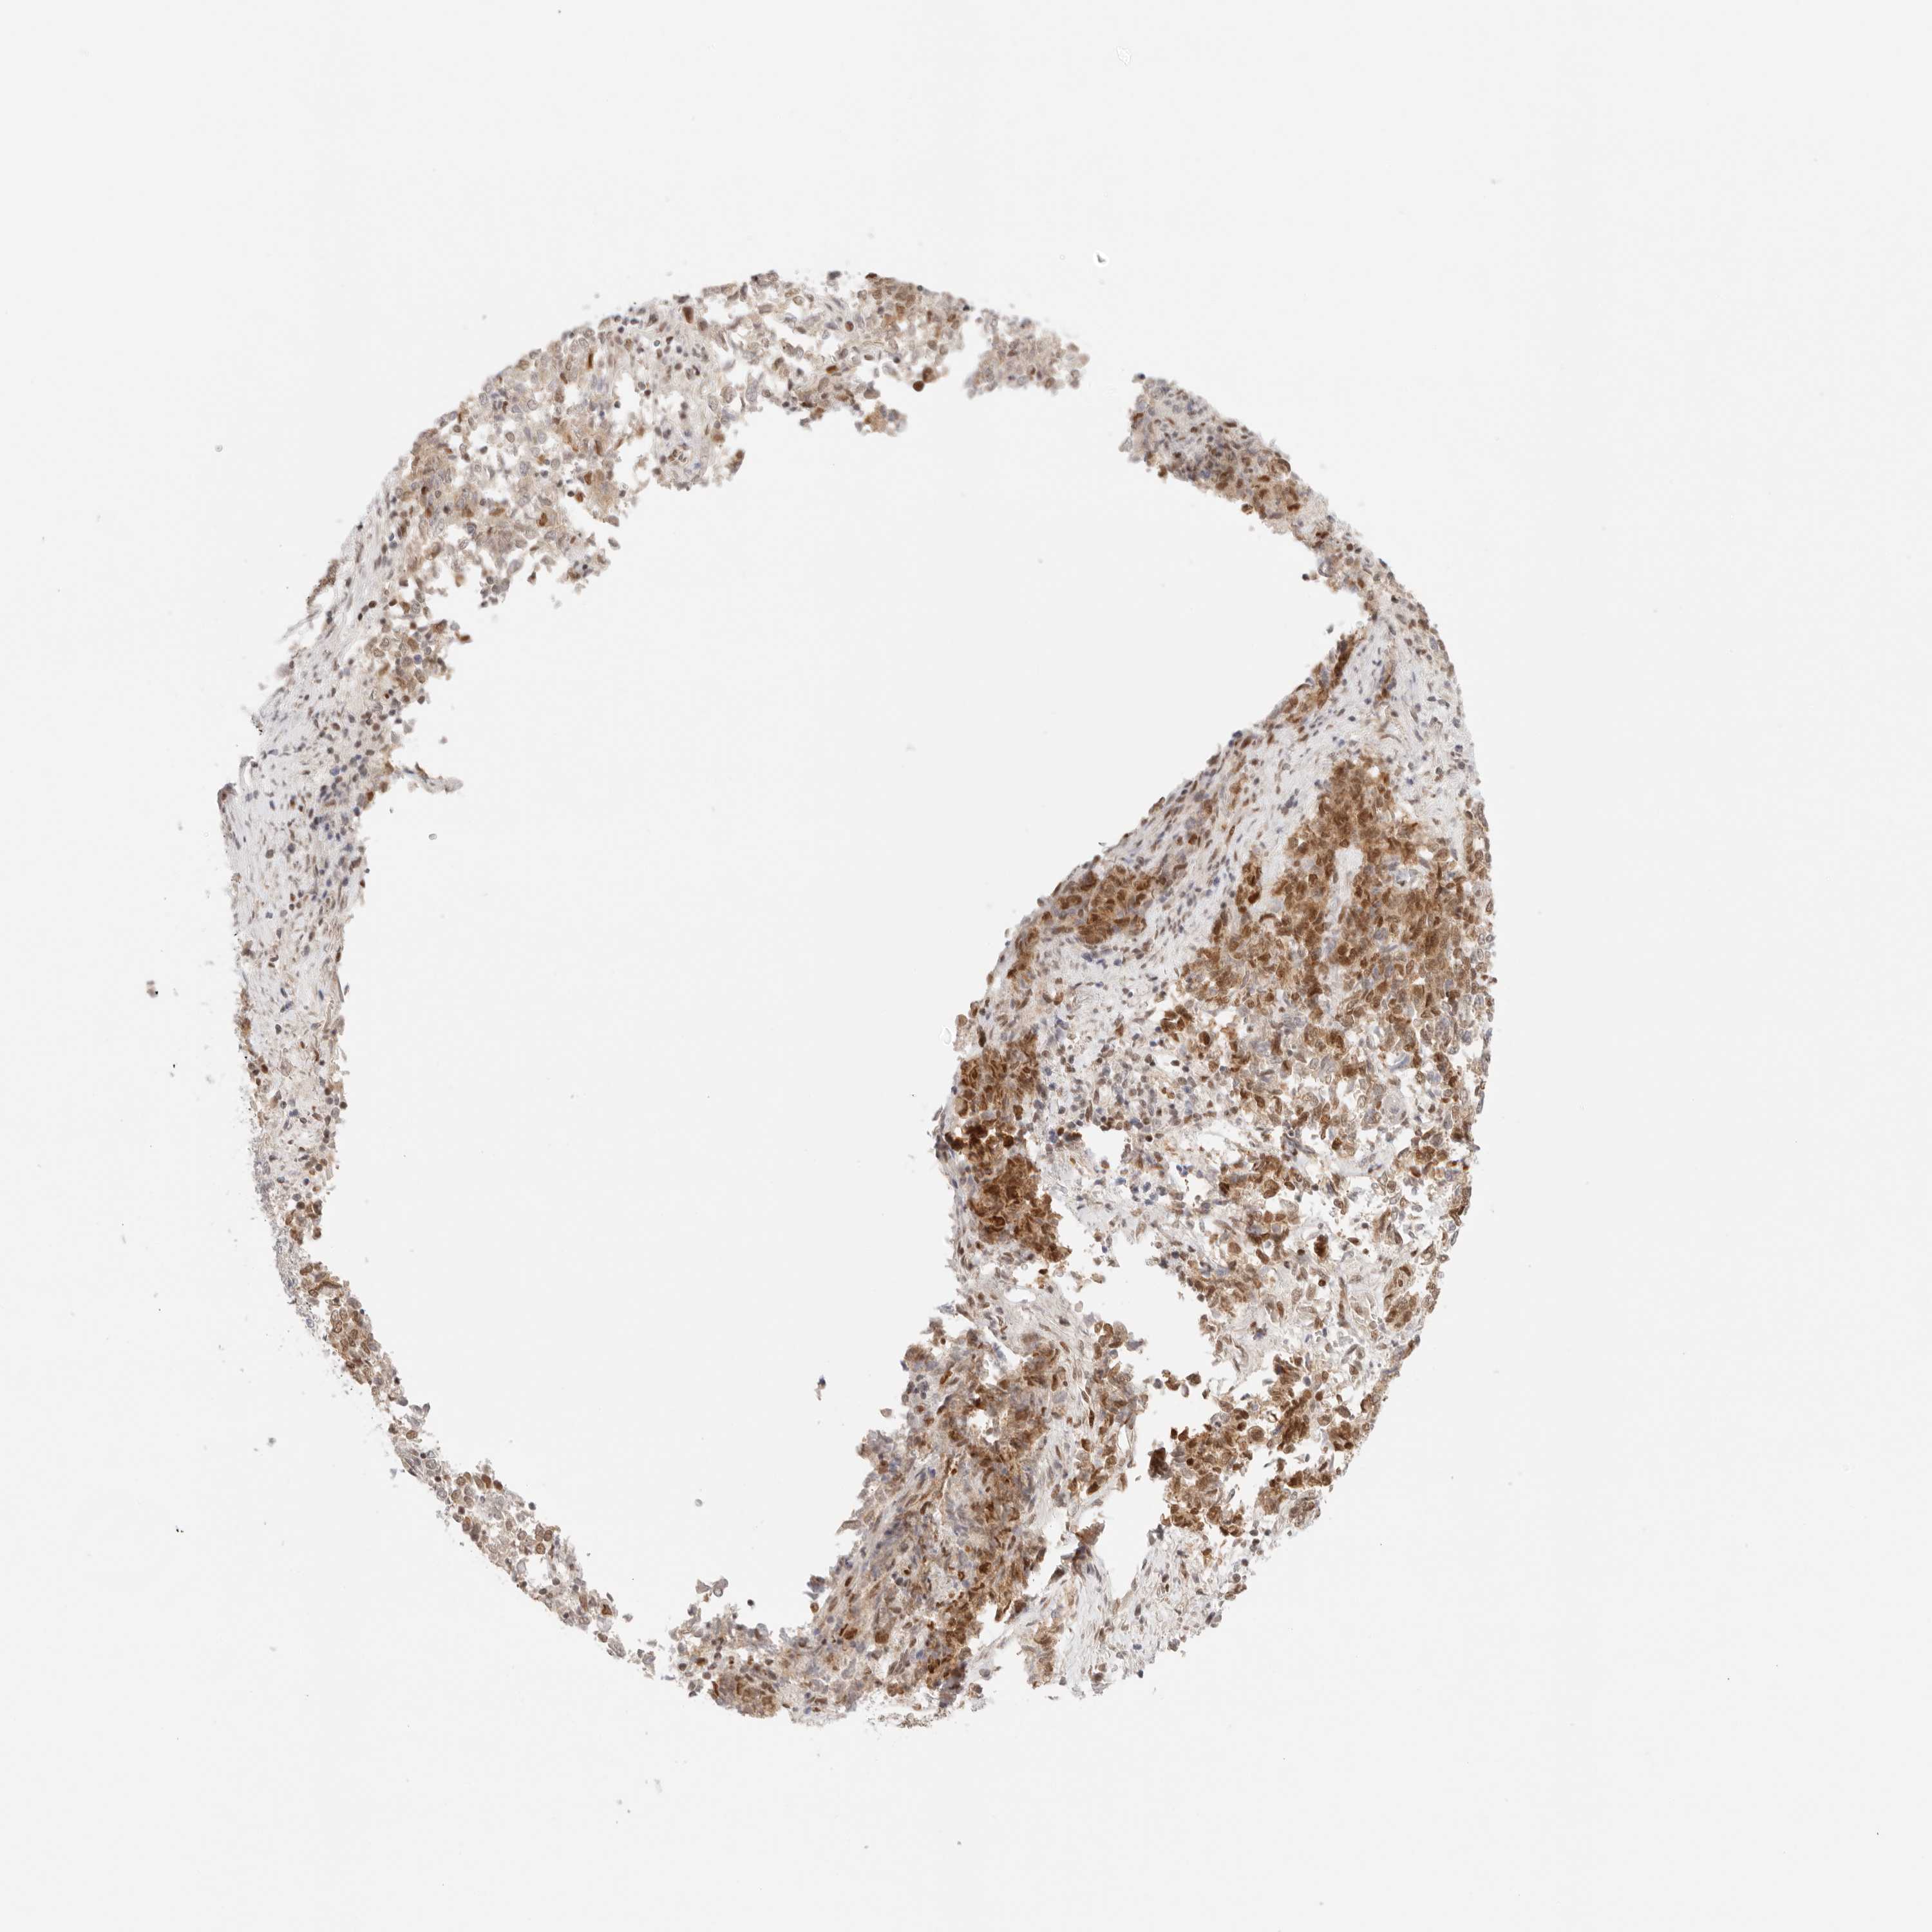

ENDOMETRIAL CANCER - Protein expressioni

A mouse-over function shows sample information and annotation data. Click on an image to view it in a full screen mode. Samples can be filtered based on level of antibody staining by selecting one or several of the following categories: high, medium, low and not detected. The assay and annotation is described here.

Note that samples used for immunohistochemistry by the Human Protein Atlas do not correspond to samples in the TCGA dataset.

Antibody stainingi

Antibody staining in the annotated cell types in the current human tissue is reported as not detected, low, medium, or high, based on conventional immunohistochemistry profiling in selected tissues. This score is based on the combination of the staining intensity and fraction of stained cells.

Each image is clickable and will lead to virtual microscopy that enables deeper exploration of all samples and also displays staining intensity scores, fraction scores and subcellular localization as well as patient and tissue information for each sample.

Antibody HPA026794

Staining

High

Medium

Low

Not detected

Intensity

Strong

Moderate

Weak

Negative

Quantity

>75%

75%-25%

<25%

None

Location

Nuclear

Cytoplasmic/membranous

Cytoplasmic/membranous,nuclear

Adenocarcinoma, NOS

Adenoma, NOS